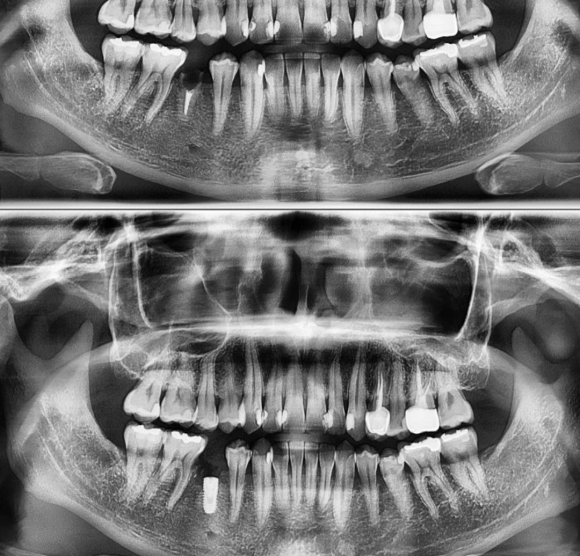

2022.4.21 previously treated tooth 의 유착 & 파절치아 난발치 후 즉시식립 저희 숭실대 입구역 리더스진 치과는 한달 평균 임플란트 60~100개를 꼼수 없이 가장 좋은 재료와 기술로 원칙적으로 식립하는 치과입니다. #상도동에서임플란트가장많이하는치과

2022.4.21 previously treated tooth 의 유착 & 파절치아 난발치 후 즉시식립

저희 숭실대 입구역 리더스진 치과는 한달 평균 임플란트 60~100개를 꼼수 없이 가장 좋은 재료와 기술로 원칙적으로 식립하는 치과입니다.